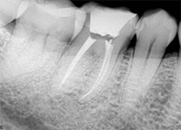

antes depois